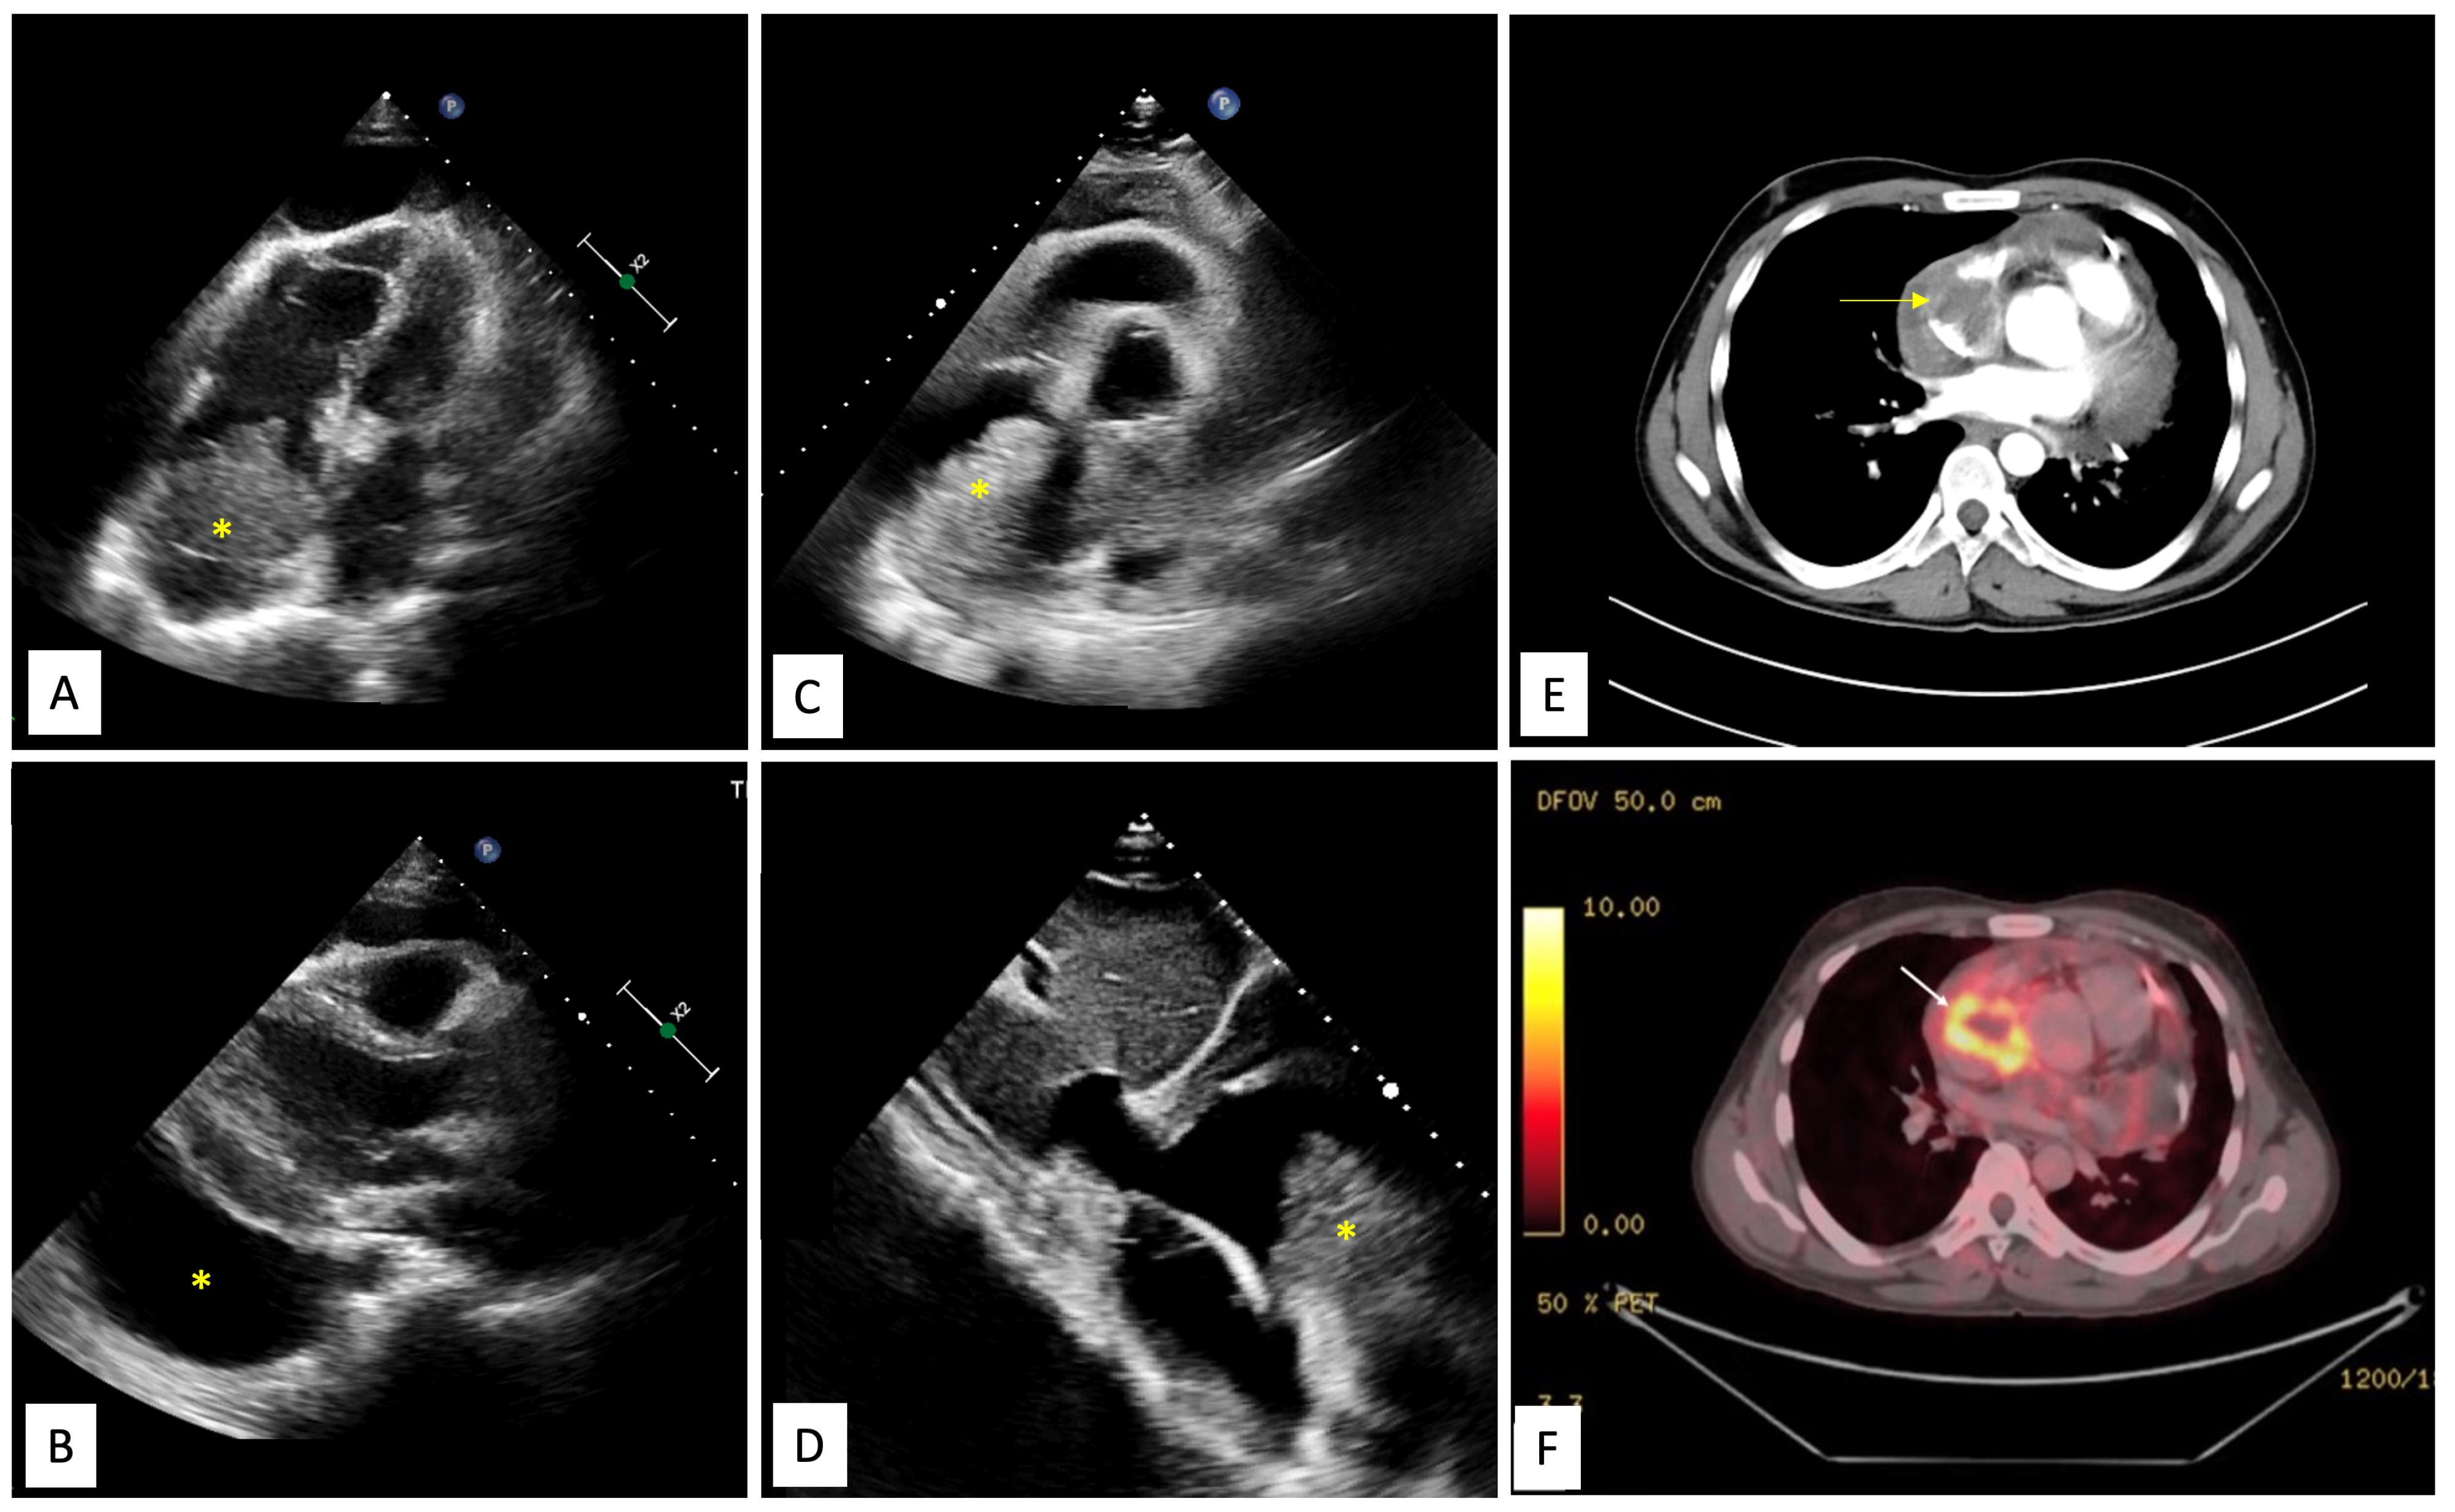

Figure 2.

Magnetic resonance imaging of the tumour. A. Balanced steady state free precession (SSFP) TRUFisp image in coronal view shows craniocaudal extent of the mass(yellow asterisk) spanning from superior vena cava (SVC)-right atrial (RA) junction cranially to acute margin of the heart. The mass is seen infiltrating into SVC (yellow arrow). Large pericardial effusion is also seen (red asterisk). B. Balanced steady state free precession (SSFP) TRUFisp image in horizontal long axis shows heterogeneous hyperintense lobulated mass (yellow asterisk) extending into the right atria and superior vena caval junction. The mass is abutting the anterior wall of RA and interatrial septum. Additionally, asymmetric loculated moderate pericardial effusion is noted (yellow arrow). C. Axial T1 non-fat saturated image reveals heterogeneous signal intensity infiltrative mass (yellow asterisk) centered along anterior right atrial wall involving pericardium and extrapericardial space.

Contrast enhanced cardiac computed tomography (CT) showed an irregular, broad-based, ‘cauliflower like’ mass abutting the lateral wall of RA with a heterogeneous streaky (sun ray) post-contrast enhancement (Figure 1E). There was local pericardial infiltration with associated moderate pericardial effusion. An aggressive mass in RA, metastasis or angiosarcoma, was suspected. There was no evidence of any primary tumor anywhere in chest or abdomen on CT scan. Cardiac magnetic resonance (CMR) imaging showed a T2-hyperintense mass measuring 64 mm x 44mm involving anterolateral wall of RA, with thickening of adjacent pericardium, superiorly invading cavo-atrial junction and extending into the superior venacava (SVC) (Figure 2A-2C). Invasion of SVC favours angiosarcoma over lymphoma; lymphoma usually presents as an insinuating mass without displacement or compression of vascular structures. The rapidly growing mass in the CMR compared to the CT image 1 week earlier, infiltration into pericardium and SVC pointed towards a rapidly growing malignant tumor. ATT was discontinued as there was a lack of improvement in symptoms and imaging evidence of likely malignancy. Positron emission tomography (PET) scan revealed an FDG-avid mass in the RA wall with extension into mediastinal structures and similar uptake in right lower paratracheal, prevascular, paraortic & paracardiac regions (Figure 1F). The mass was seen to infiltrate ascending aorta, pulmonary artery and SVC. It showed areas of photopenia & hypodensity within mass, suggestive of necrosis. No metastasis to distant organs was noted. Patient had further deterioration of dyspnea and in search of a definitive diagnosis, an endomyocardial biopsy was planned after discussion with heart team. The tissue analysis, however, did not yield any malignant cells. After discussion with the family, open biopsy using a lateral thoracotomy approach was performed. A few hours after the procedure, patient had sudden and rapidly progressive shock and worsening of respiratory distress requiring mechanical ventilation. Echocardiogram revealed large pericardial effusion with tamponade, which on aspiration yielded hemorrhagic fluid. With a possibility of active bleed from the vascular tumor or a vessel, a midline thoracotomy was done to localize and stop bleeding. The patient’s hemodynamics worsened during the procedure and he succumbed. Histological examination of the biopsied tissue revealed large areas of hemorrhage with fibrin & necrosis. Preserved areas showed a tumour arranged in sheets and short intersecting fascicles. There were slit like spaces with red blood cells. Tumor cells were moderately pleomorphic, had round-to-oval nuclei with vesicular chromatin, conspicuous nucleoli and moderate amount of cytoplasm. These cells were positive for CD31(membranous) and negative for desmin and PanCK(pancytokeratins) which was suggestive of angiosarcoma.